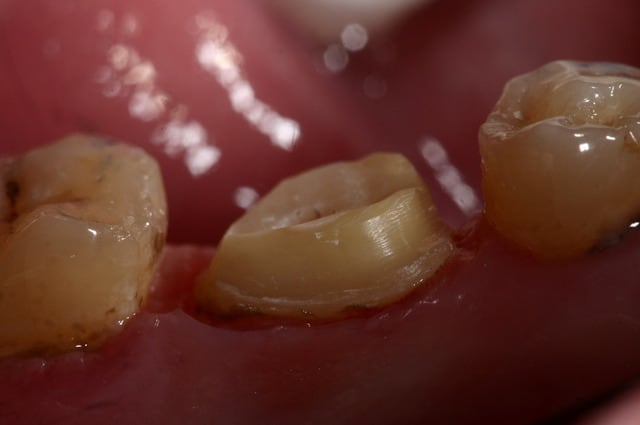

pour enfoncer le clou sur les tenons et autre inlay core

ne pas perdre de vue qu'un tenon = Rétention ... c'est tout !

Si on a de la rétention autrement, pas besoin de tenon...

Un tenon fragilise la racine et réduit l'étanchéité du traitement endo...

un cas comme on peut en faire souvent, d'endo couronne collée, exploitant le volume de la chambre pulpaire...

Et j'ajouterais que sur les photos que tu nous montres, tu as as réalisé un trottoir périphérique, pour réaliser qqchose qui ne correspond pas à la définition traditionnelle d'une endocouronne (qui est en réalité un onlay, avec prise de rétention interne).

Il est possible que l'ajout de férule par ce moyen permette au dispositif de fonctionner, mais dans ce cas, quel intérêt par rapport à une reconstitution composite avant couronne traditionnelle ?

C'est pas mal comme restauration, toutefois, tu as eu un peu de chance car l'endocouronne ne se prépare pas comme cela.

Tu a fais un mix entre la coiffe périphérique et l'endocouronne et il y a des risques de casse accrus. C'est dommage pour ces restaurations qui sont totalement inaltérables. Ce type de confusion dans les formes de préparations est très fréquent au début, et même un peu plus tard dans l'exercice. Il est certain que l'on a beaucoup de mal a lâcher les angrammes des restaurations classiques

Une endocouronne utilise le plancher caméral et sa forme de selle qui ne doit pas être fraisé et les parois sont ouvertes avec un maximum de 7° de TOC inversée.

La périphérie aplanie est si possible parallèle au plan occlusal ou perpendiculaire au sens d'application des forces.

Pour répondre a ta réponse je fait endo couronne quand le volume de la chambre est superieur au volume du futur moignon ... j'ai fait des photos très parlantes que je retrouve plus :(

photo retrouvées :)

plus de place pour la ceramique, et plus de rétention dans l'endo que dans l'exo ;)